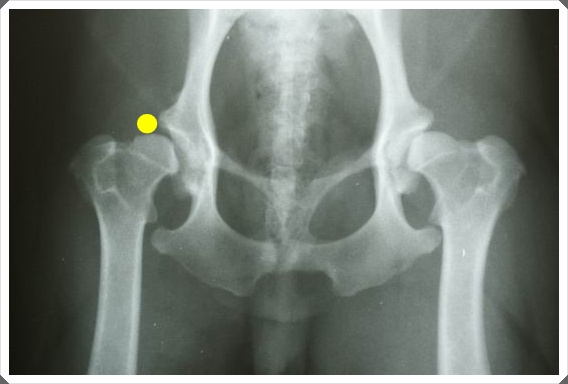

如果以下面這張來看的話,左腳是是整個包覆著屬於正常的,右腳才有髖關節不在圈圈內...

也就是黃點的位置,只要他一動右腳的話,就會磨擦到而感到疼痛,導致不敢使用!